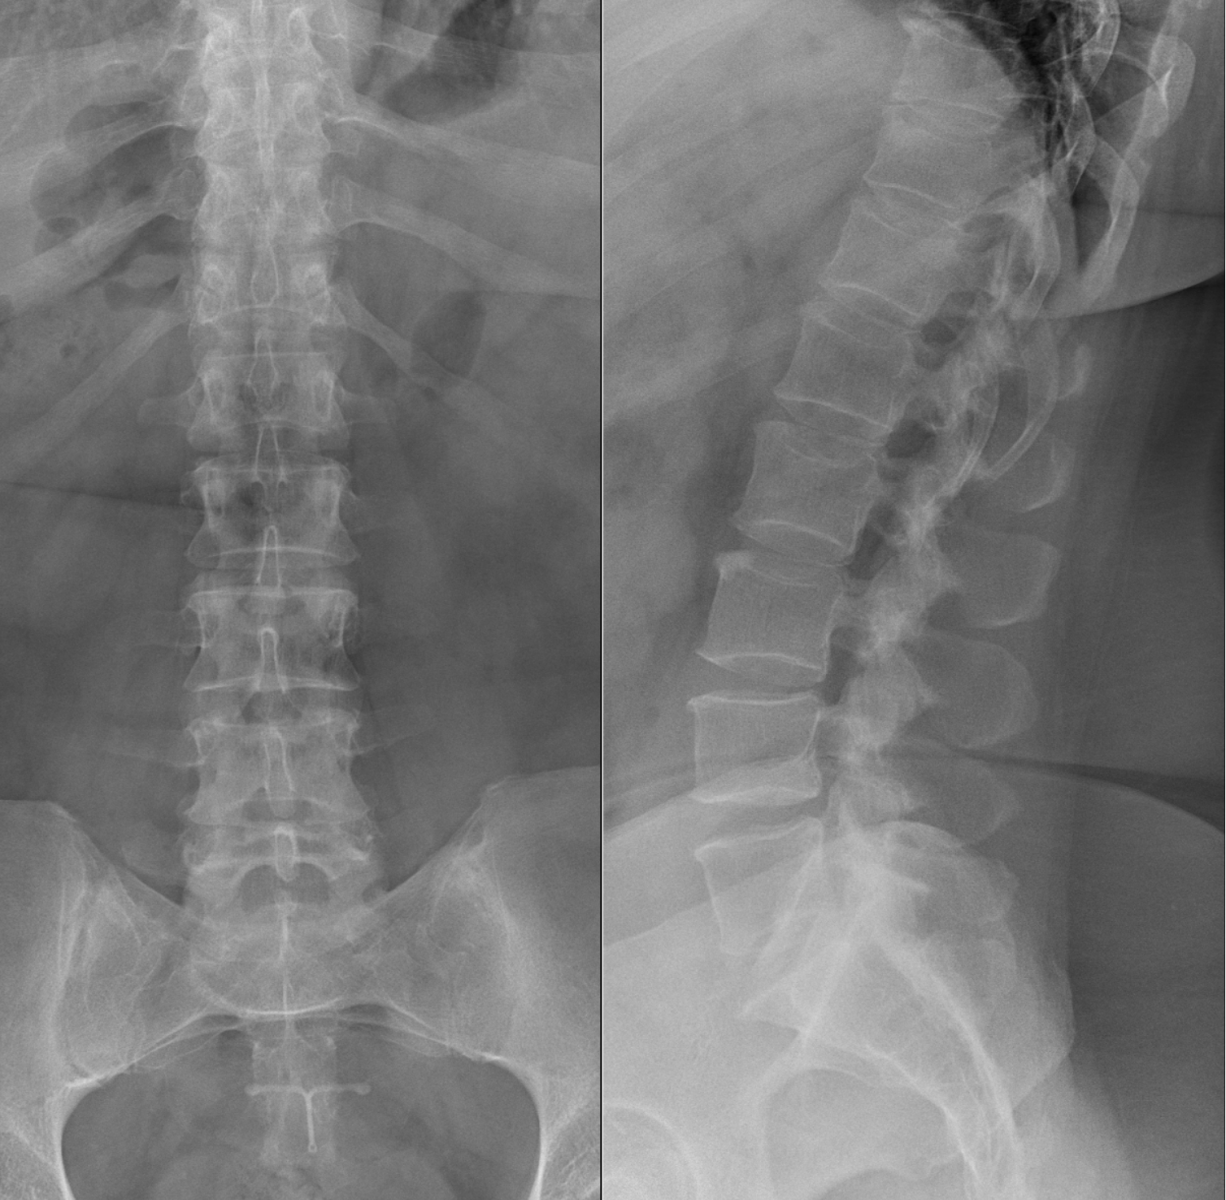

Princip vyšetření je založen na schopnosti rentgenového záření pronikat hmotou a dle vlastností jednotlivých tkání se specificky zeslabovat. Výsledkem je obraz zachycený na citlivý materiál – rentgenový film či detekční systém přístroje. Rentgenové vyšetření se hodí zejména k posouzení kostí a plic. Dále je možné např. z obsahu plynu ve střevech posoudit průchodnost střeva. Na snímcích lze hledat cizí kovová tělesa v těle.

Provádíme kompletní spektrum základních i speciálních skiagrafických vyšetření skeletu i měkkých částí lidského těla.

Ukázky RTG snímků